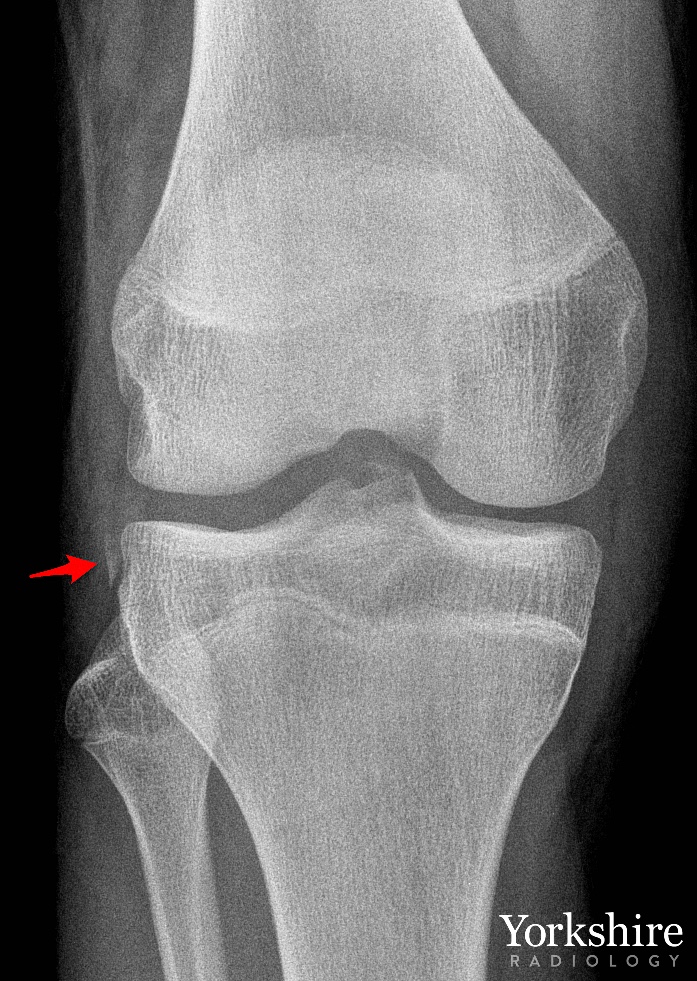

Small fracture - big injury. The radiograph shows a small avulsion fragment, commonly known as a Segond fracture. Well over 90% of patients with this finding will also have an ACL rupture. Learn more about knee anatomy and injuries @arthroinsights #FOAMed #FOAMrad #orthotwitter